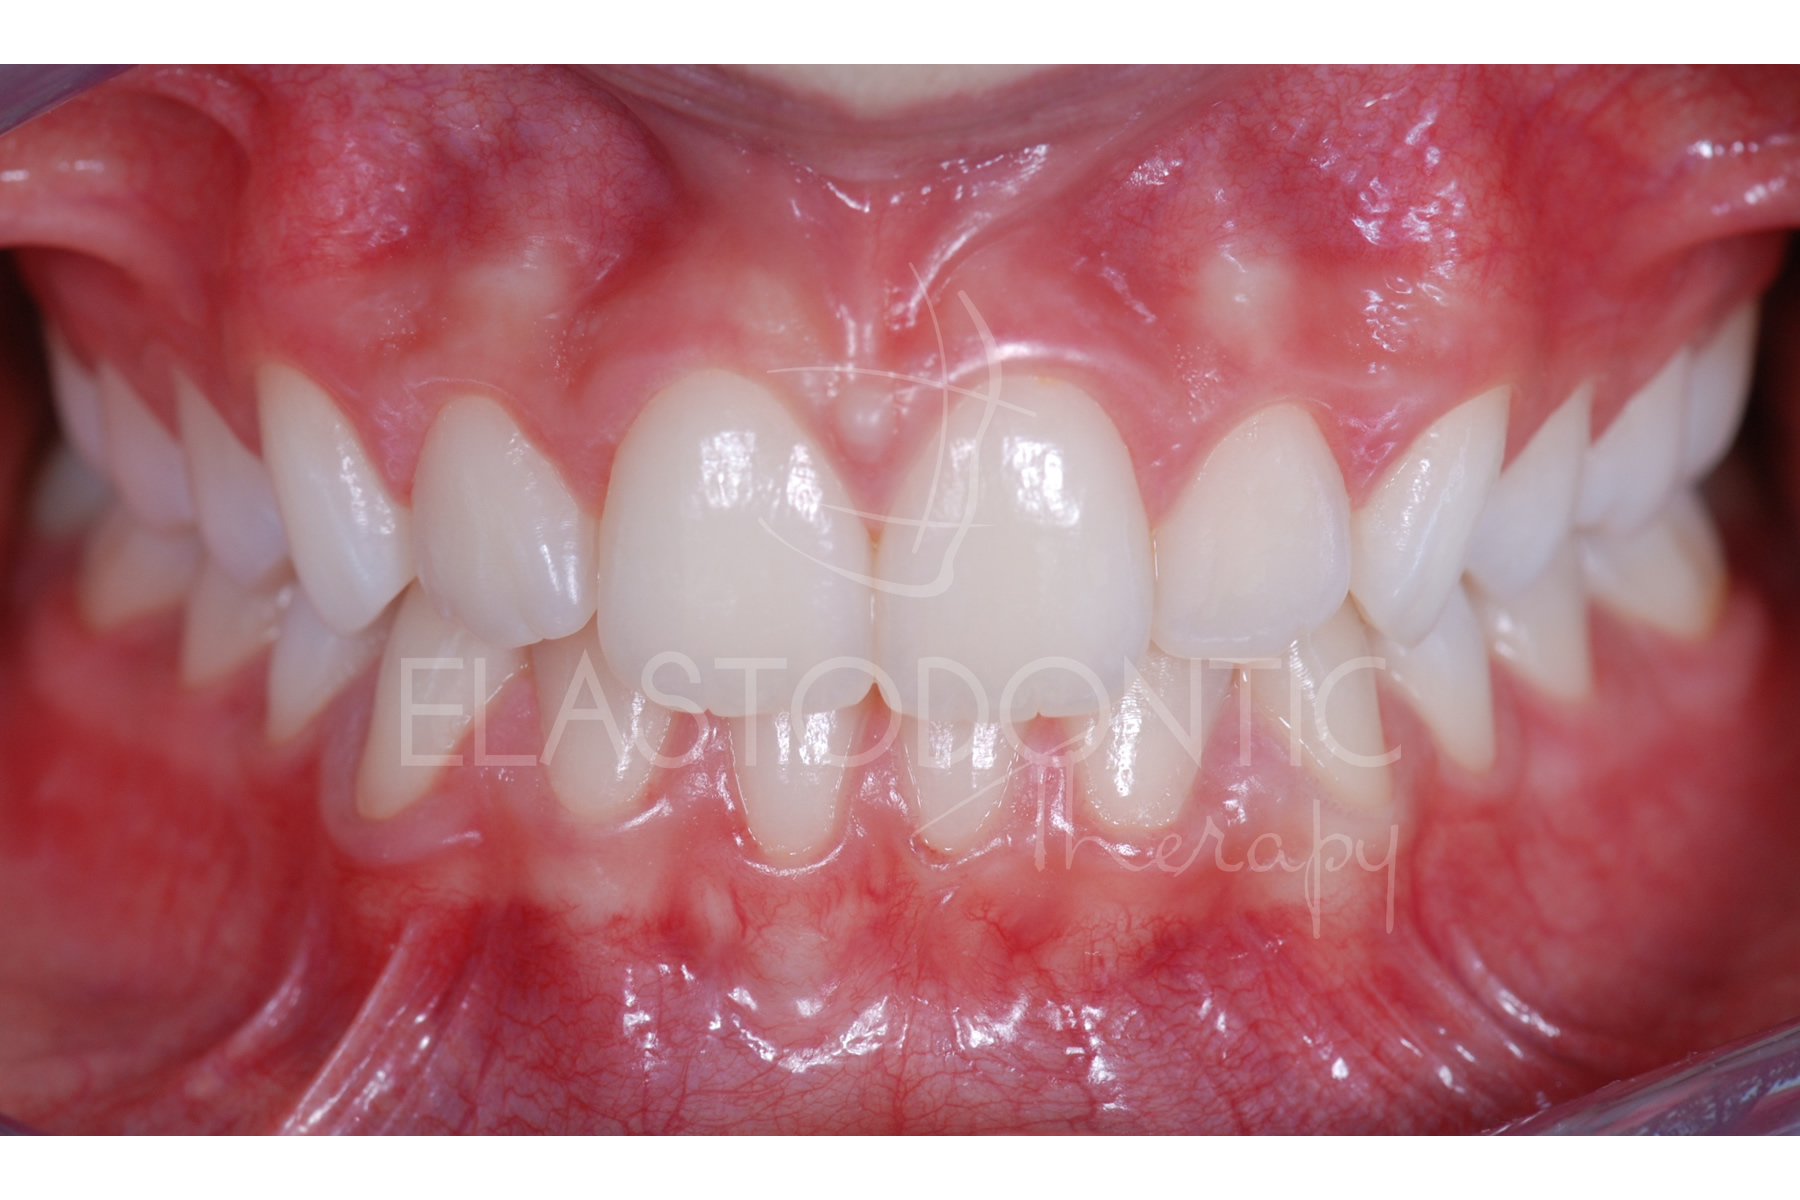

Denti Affollati

Paziente di 9 anni.

Affollamento arcata inferiore.

Trauma occlusale.

Danno parodontale.

L'Elastodontic Therapy® iniziata all'età di 9 anni, ha permesso di correggere la malocclusione in pochissimi mesi con l'ausilio di un SOLO apparecchio elastodontico e cosa importante senza ricorrere ad estrazioni che avrebbero compromesso il risultato estetico della terapia.

La stabilità nel tempo è garantita dal raggiungimento di un ottimo rapporto occlusale fisiologico e biologicamente determinato.